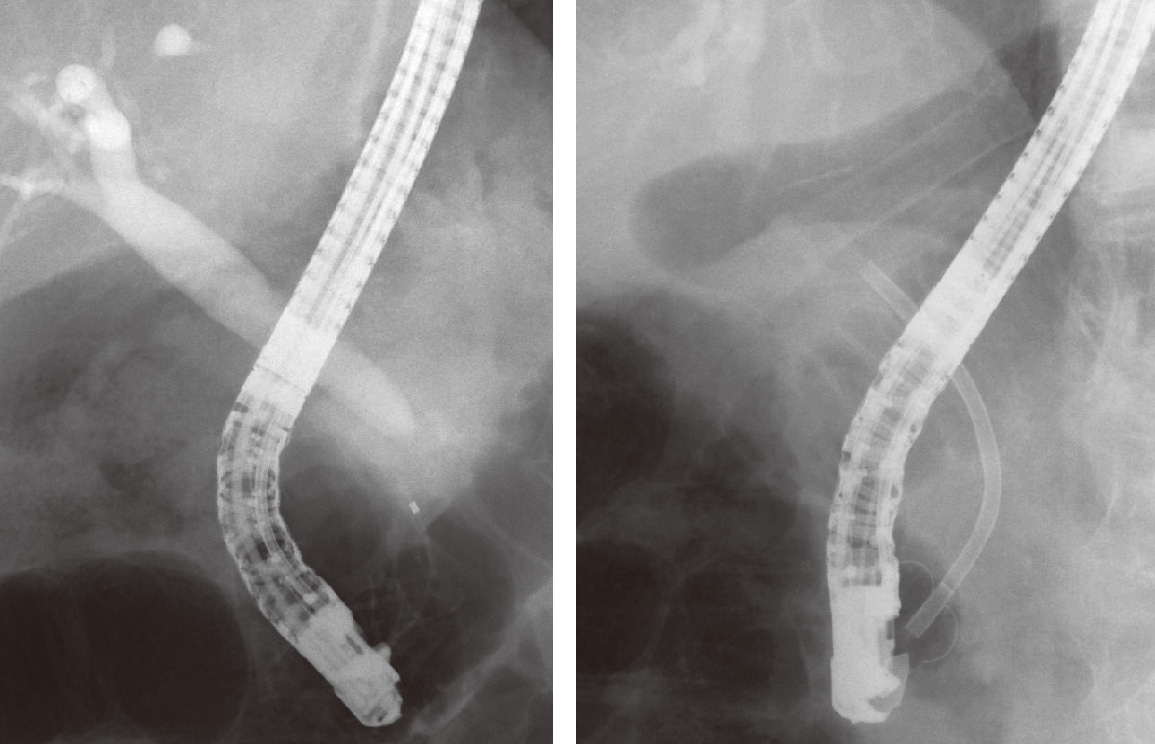

ⓔ図12-25-12 チューブステントによる内瘻化

良性胆管狭窄に対しプラスチックステントを留置した.